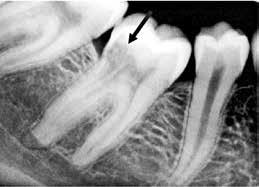

Fig. 11. A. Skematisk illustration af tand med pulpasten i pulpakammer og rodkanaler, hvilket kan gøre det vanskeligt at lokalisere kanalindgangene og udrense kanalerne (18). B. Bitewing-optagelse viser generaliseret dannelse af pulpasten i molarerne (pile). C. Periapikal optagelse af -6 med omfattende forkalkninger i pulpakammer og rodkanaler (pil).

Fig. 11. A. Schematic illustration showing tooth with pulp stone in the chamber and root canals creating potential difficulty in locating root canal orifices and instrumentation (18). B. Bitewing radiograph showing generalized pulp stone formation on molars (arrows). C. Periapical radiograph of mandibular left first molar with extensive calcifications in the pulp chamber and root canals (arrow).